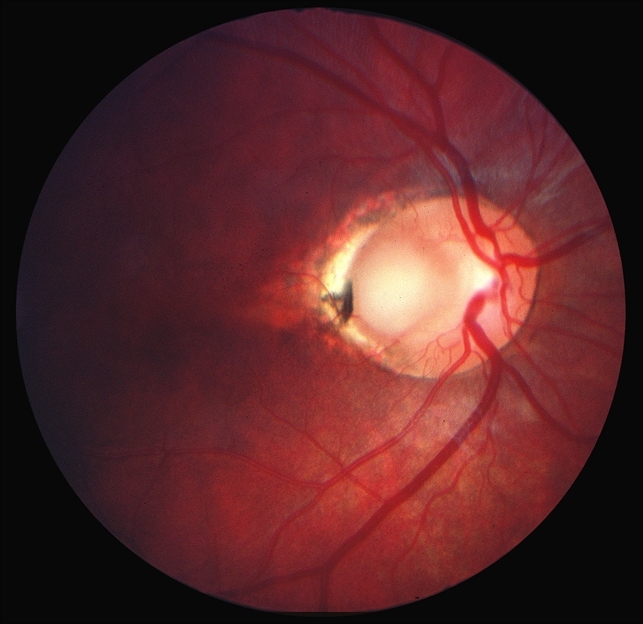

Диаметр ямок диска зрительного нерва варьирует от 1/3 до 1/8 РД. Заболевание чаще одностороннее. Билатеральные ямки диска зрительного нерва встречаются в 15 % случаев. При одностороннем поражении аномальный диск кажется слегка увеличенным по сравнению с нормальным.

Серозная отслойка сетчатки возникает преимущественно при ямке диска височной локализации. Эта отслойка имеет каплевидную форму и начинается от височного края диска, распространяясь на область макулы, иногда захватывает весь задний полюс, не выходя за пределы темпоральных сосудистых аркад.

Эта аномалия диска часто сочетается с врожденным перераспределением пигмента в перипапиллярной области и наличием цилиоретинальной артерии (59 %случаев). Область ямки может быть прикрыта сероватой мембраной с множеством отверстий.